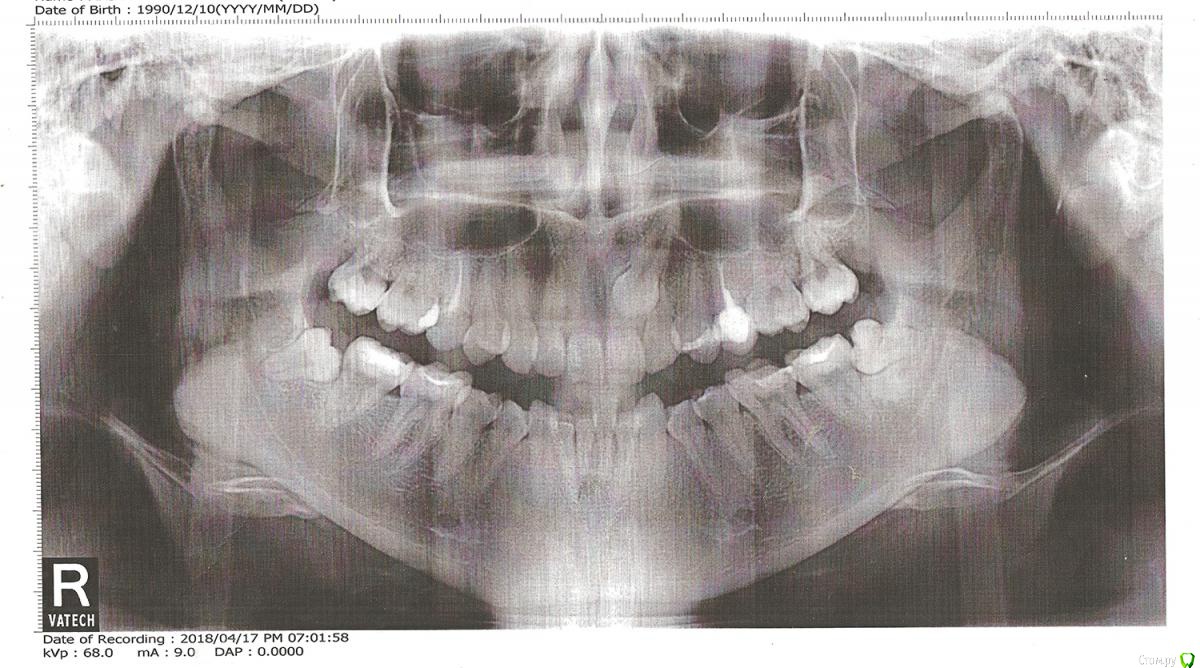

Здравствуйте.

Сломана левая верхняя 5, восстановлению не подлежит, естественно, предлагают имплантацию. А у меня с этой стороны ретинированный клык. Возможно ли вместо имплантации вытащить этот клык, дав сместиться 4 на место 5?